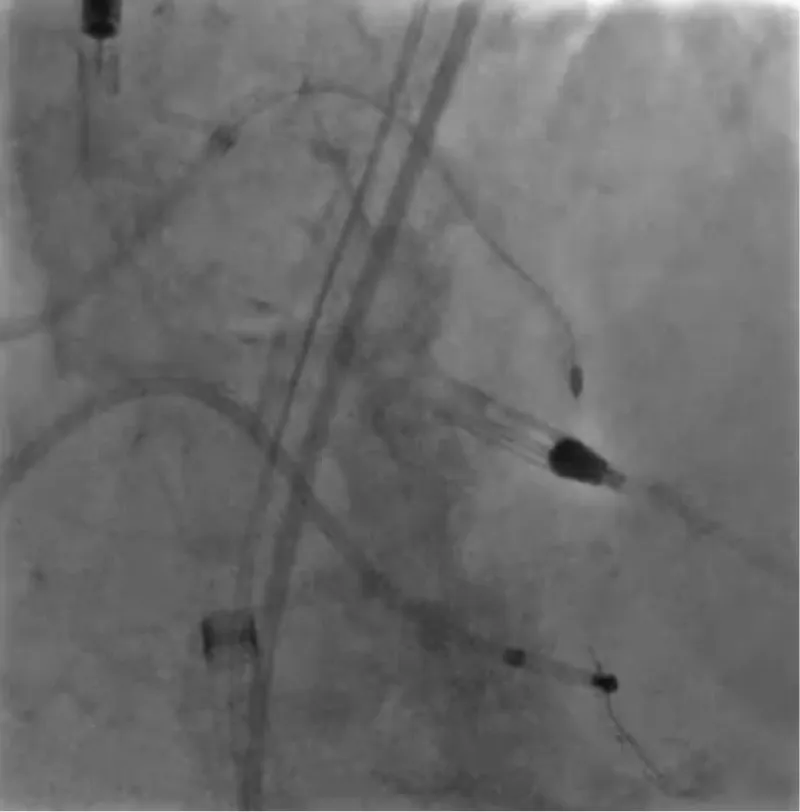

The clinical case concerns an 81-year-old woman with a history of systemic arterial hypertension, hypercholesterolemia, paroxysmal atrial fibrillation, chronic kidney disease, iron-deficiency anemia, and bilateral carotid atheromatosis for which she underwent a Carotid Endarterectomy (CEA) procedure. Additionally, she had a history of breast carcinoma, treated with surgery, subsequent chemotherapy, and ongoing Letrozole therapy. In 2019, the patient presented to the emergency department due to exertional dyspnea and low-threshold angina. During hospitalization, high average ventricular response (109 BPM) atrial fibrillation was diagnosed. Routine lab tests showed rising of hsTN-I (peak 800 pg/dL) and pro-BNP (peak 2476 pg/mL) and anemia Hb 9.1 g/dL. Echocardiography revealed severe depression of the left ventricular function (ejection fraction of 30%, with antero-apical akinesia) and low-flow-low-gradient aortic stenosis (mean gradient of 26 mmHg and AVAi of 0.5 cmq/m2 and SVi 29 mL/m2). So it was performed a Dobutamine stress Echo showed a rise of SVi up to 38 mL/m2 and a mean aortic gradient of up to 48 mmHg. Coronary angiography showed the right dominant coronary artery, of good caliber and course, with no angiographically significant lesions (Figure 1). The Left Main artery, with good caliber, had a 90% calcific stenosis at the distal segment, involving the proximal segment of the Left Anterior Descending artery. The Left Circumflex artery, with good caliber and course, presented a 30% ostial stenosis. The Intermediate Branch, with good caliber and course, showed 80% stenosis at the proximal segment (Figure 2). The Left Anterior Descending artery, also of good caliber and course, was diffusely atherosclerotic with a long, severely calcific 80% stenosis at the mid-distal segment (Figure 3). Therefore, the case was discussed by a multidisciplinary Heart team at our center. The STS score calculated indicated a mortality risk of 11.4%. Due to this high risk, surgical treatment was not considered, and the patient underwent a four-step percutaneous intervention. Before the intervention, a CT angiography was performed, revealing an aortic annulus area of 433.2 mm2, a perimeter of 75.3 mm, and a coronary height from the annulus of 10 mm. The right common femoral artery mean diameter was 6.1 mm2 and the external iliac artery was 8.4 mm2 with moderate tortuosity without significant calcification (Figure 4-6). Therefore, a 23 mm Edwards Sapien 3 valve was chosen. Our strategy consisted of 4 steps:

Figure 1: Right dominant coronary artery, of good caliber and course, with no angiographically significant lesions.